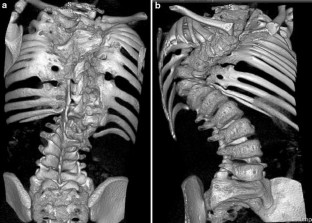

In this Grand Round, we present the case of a 7-year-old girl with a severe scoliosis and thoracic insufficiency syndrome (TIS). 3D CT reconstruction imaging demonstrated a mixed picture of fusion and segmentation abnormalities. A marked kyphoscoliosis was demonstrated at the thoraco-lumbar junction. Via a left thoracotomy, anterior excision of intervertebral discs was performed together with, interbody fusion, and in situ stabilisation of the kyphosis with double allograft (femur) strut grafts.